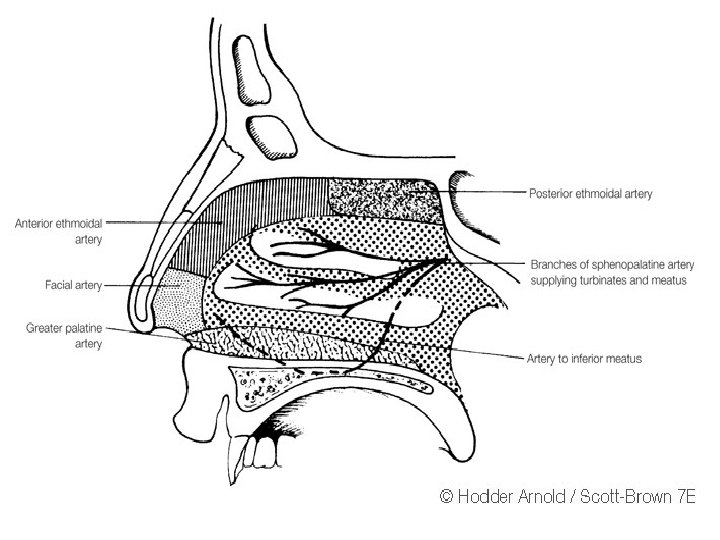

• Blood supply: facial and ophthalmic arteries and veins • Lymphatic drainage: preauricular and submandibular lymph nodes